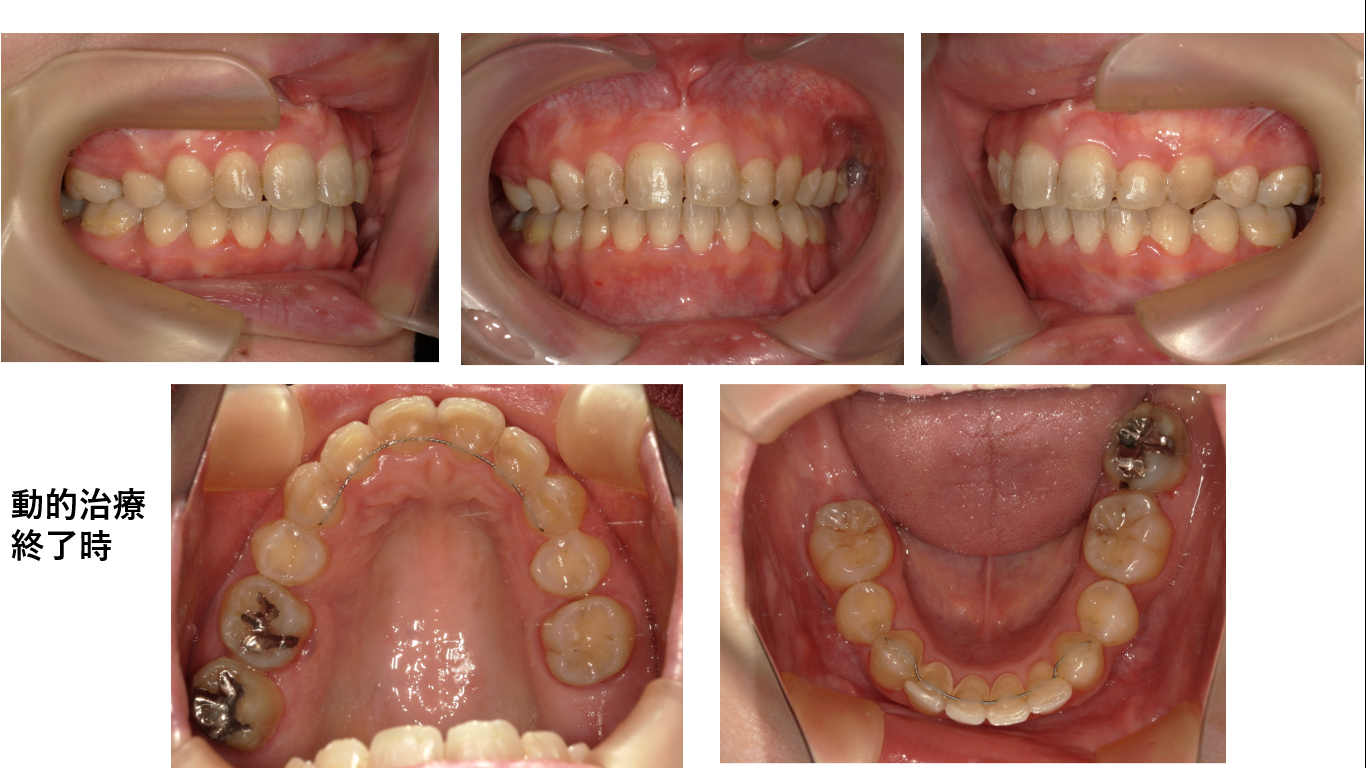

矯正症例145 叢生を伴うAngleⅡ級1類上顎前突

初診時34歳女性、治療期間4年2か月、抜歯部位:上顎左右5番、下顎左右5番、治療費総額112万円(税込み)

下顎歯列弓が重篤なv字歯列弓です。これを修正するのに通常の矯正より時間がかかります。更に初診時34歳の年齢であることから時間が大幅にかかります。

右上7番は歯肉縁下カリエスで抜歯となりました。動きが遅い症例でしたが、コルチコトミーを併用しても良かったと思っています。